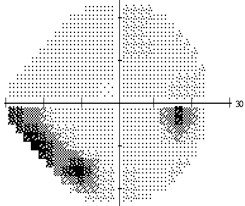

– une acuité à 8/10 aux deux yeux avec une correction de -2,5 -1 à 90° à droite et -1,75 -1,25 à 85° à gauche ;

– une tension oculaire mesurée au tonomètre de Goldmann à 22 mmHg pour une pachymétrie épaisse ;

– une vision de près p4 aux deux yeux avec une addition de 2,75 dioptries, malgré la lecture de lettres ondulées.